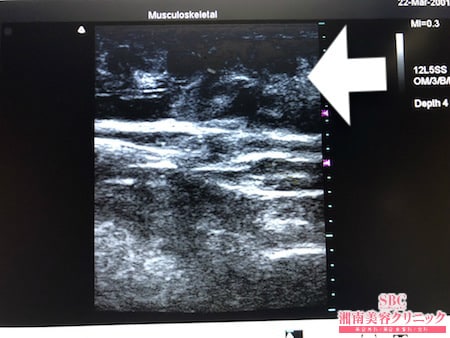

No.235811【脂肪吸引】【動画あり】湘南美容外科脂肪吸引最高責任者である竹田先生による脂肪吸引のフォトギャラリー!近所の美味しいパン屋さんのパンを食べ続けて1年で12kg太った患者様のおなかの皮下脂肪を根こそぐ!術中3Dタッチビュー・左腰